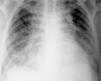

Edema pulmonar fatal en paciente con meningitis por enterovirus